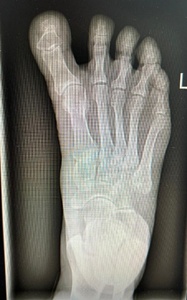

Radiographic evaluation demonstrated effective correction of the hallux alignment. The mean hallux valgus angle (HVA), which was negative in all cases preoperatively (mean –16.5° ± 4.2), improved significantly to a postoperative mean of 5.7° ± 3.2 (p = .0156), with all patients achieving alignment within the physiologic range. Representative radiographs are presented in Figures 1 and 2.

Patient Satisfaction

All patients expressed subjective improvement in foot function, pain, and appearance. Five patients rated their outcomes as “completely satisfied,” and two were “satisfied with minor concerns.” No dissatisfaction or requests for additional surgical revision were recorded. Representative pre- and postoperative clinical photographs illustrating cosmetic improvement in toe alignment are shown in Figure 3.